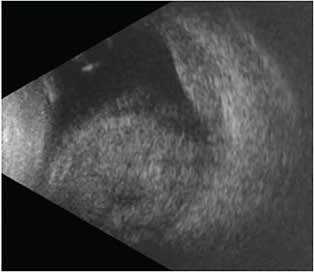

A 73-year-old female experienced an expulsive choroidal hemorrhage in her right eye during topical cataract surgery after having sudden, severe coughing during phacoemulsification. A PC tear occurred, necessitating an anterior vitrectomy and sulcus IOL placement, at which point a suprachoroidal hemorrhage was noted. At clinic the same day, the patient noted significant eye pain alongside hand motion visual acuity and an IOP of 11. There were large hemorrhagic non-kissing choroidals, a vitreous hemorrhage, and a flat retina best appreciated by B scan (Figure 3). Medical management similar to Case 1 was employed with close follow up.